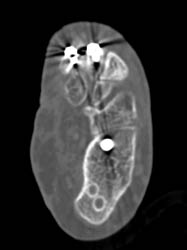

Thigh Hematoma